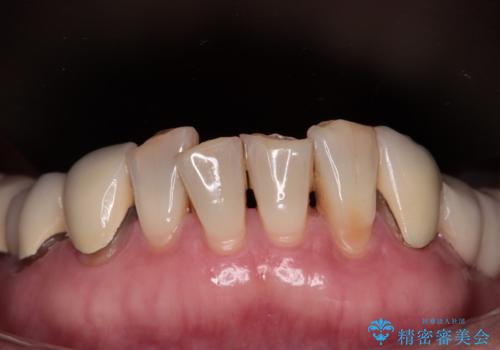

- 歯肉ラインの段差や、歯根が黒く見えている前歯を気にして来院された患者様です。

前歯のインプラントは埋入されたポジションが望ましい位置ではなく、インプラントを活用して段差を回収することは不可能と判断し、歯肉移植によりインプラントを隠して、ブリッジにて歯肉ラインを整えることとしました。

臼歯部の治療も必要と判断されましたが、前歯部を中心とした審美領域をオールセラミッククラウンによる補綴治療を行うこととしました。